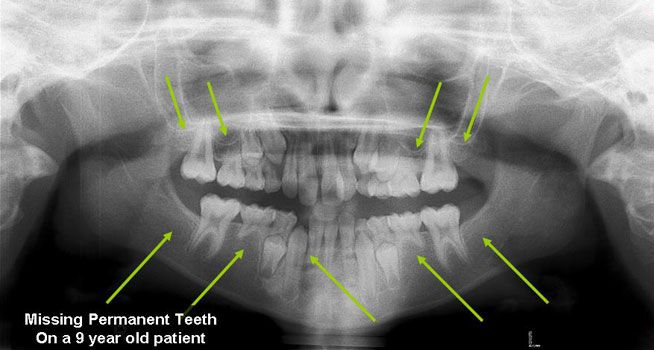

Missing Permanent Teeth

Hypodontia (the common dental term) describes a situation when fewer than 6 permanent teeth are missing, the term Oligodontia is used when more than 6 permanent teeth are missing (they were never formed). The most common missing teeth are the third molars (otherwise known as the Wisdom Teeth), followed by the premolars and the lateral incisors. Although it is not uncommon to have one missing tooth, patients with multiple missing teeth generally have a strong genetic component and it has been linked to conditions such as Ectodermal Dysplasia and several syndromes. Because early recognition aids in proper treatment, your dentist will refer you to specialists (orthodontist, oral surgeons, etc) that will determine which options suit you best to replace the missing teeth.

X-ray of missing teeth